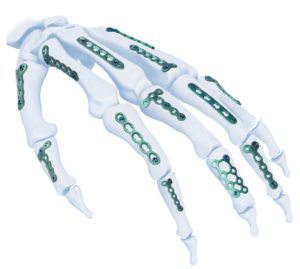

SISTEMA AIMIMINI VAL PARA MANOS 1.5/2.4/2.7 BLOQUEADO

El implante AIMIMINI val hand mini lock system se puede utilizar para la fijación temporal, corrección o estabilización del bloque óseo en la posición anatómica de la mano.